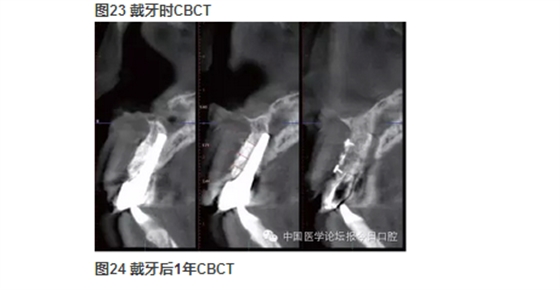

北京大學(xué)口腔醫(yī)院種植科 在唇側(cè)和舌側(cè)牙槽突骨板骨折的病例中,唇/舌側(cè)牙槽突發(fā)生相應(yīng)的骨吸收。長期的臨床經(jīng)驗告訴我們,唇側(cè)和舌側(cè)骨板的低位骨折,任其常規(guī)牙槽窩愈合,會導(dǎo)致三維方向的骨缺損。根據(jù)ITI機構(gòu)的SCA分類,伴有垂直和水平骨缺損的病例,則是復(fù)雜和高難度病例,美學(xué)風(fēng)險極大。即刻種植無法預(yù)防和避免骨吸收。 在本病例中,我們采用符合富血小板纖維蛋白(PRF)技術(shù)的牙槽窩位點保存技術(shù),最大限度保存局部骨量。以及采用輪廓擴增的引導(dǎo)骨再生(GBR)技術(shù)同期種植重建了種植位點的三維骨結(jié)構(gòu),通過暫時冠誘導(dǎo)穿齦輪廓和牙齦乳頭形態(tài),最終獲得患者滿意的美學(xué)修復(fù)。 女性,27歲。以“右上前牙樁冠修復(fù)11年,脫落1周”為主訴前來就診。 11年前,患者前牙外傷,于當(dāng)?shù)蒯t(yī)院行11、21、22根管治療及11樁冠修復(fù)。1周前11樁冠脫落,于多家醫(yī)院修復(fù)科就診,以“11牙槽突骨折”的診斷,無法保留11殘根,建議拔除,而前來就診。 既往體健,否認(rèn)系統(tǒng)性疾病史及藥物過敏史。 臨床檢查可見11殘根,21、22牙冠變色。前牙區(qū)咬合略緊,Ⅱ度深覆牙合。CBCT示上頜右側(cè)中切牙頰側(cè)根頸1/3骨板折裂。21、22牙冠變色。前牙區(qū)咬合略緊,Ⅱ度深覆牙合。CBCT示上頜右側(cè)中切牙頰側(cè)根頸1/3骨板折裂。21、22根尖病變,前牙區(qū)牙槽突根方骨量不足。 圖6 舌側(cè)骨缺損的3D重建 診斷 ①右上中切牙牙槽突骨折(?);② 左上中切牙、側(cè)切牙慢性根尖炎;③Ⅱ度深覆牙合。 病例特點與難點 ①樁冠修復(fù)失敗后的三維骨缺損(頰/舌側(cè)骨板折裂、牙槽骨根方骨量不足);②年輕女性,美學(xué)要求較高;③ 鄰牙根尖周病變;④輕度深覆牙合,咬合略緊。上頜骨基底骨骨量不足,正畸醫(yī)師不建議矯正。 治療設(shè)計 ①正畸會診,希望下前牙下壓,改善咬合緊,深覆牙合;② 左上中切牙、側(cè)切牙根管治療,必要時行根尖手術(shù),貼面修復(fù)改善美觀;③ 右上中切牙牙槽窩位點保存,根據(jù)牙槽嵴骨量保持情況,確定二期種植和植骨以及必要的軟組織整理和塑形。 1.正畸科醫(yī)師會診,因患者上頜牙槽骨基底骨骨量不足,多數(shù)牙齒唇側(cè)骨板不足或缺失,正畸風(fēng)險大而建議放棄正畸治療。 2.因無法進(jìn)行正畸治療,故需要合理的種植位點和修復(fù)方式,以適應(yīng)患者的咬合情況。 3.牙體牙髓科醫(yī)師會診,進(jìn)行左上中切牙、側(cè)切牙根管治療后隨訪,根據(jù)愈合情況決定是否進(jìn)行根尖手術(shù)。 4.右上中切牙牙槽窩位點保存+富血小板纖維蛋白(PRF)技術(shù)。 5.6個月后行種植+引導(dǎo)骨再生(GBR)。 6.愈合4個月后,行軟組織增量和塑形,擇期永久修復(fù)。 7.愈合期內(nèi),以馬里蘭橋或壓膜過渡義齒臨時修復(fù)。 8.左上中切牙、側(cè)切牙貼面修復(fù)改善美觀。 ④ Bio-Oss®; ⑤ NobelProcera全瓷修復(fù)。 ①左上中切牙、側(cè)切牙經(jīng)根管治療后,根尖病變隨訪期內(nèi)縮小并逐漸消失,避免了進(jìn)一步的根尖手術(shù); ②右上中切牙牙槽窩位點保存+PRF技術(shù)治療,避免了牙槽嵴可能發(fā)生的三維方向骨缺損,極大限度保持和原位重建局部骨量; ③在種植位點軟組織和硬組織無缺損的情況下,在較佳的三維位點植入種植體,同期GBR行輪廓擴增的骨增量技術(shù),應(yīng)用低替代率的骨代用品,獲得較好的長期穩(wěn)定性; ④左上中切牙、側(cè)切牙貼面修復(fù)美學(xué)效果較好; ⑤經(jīng)過治療和口腔健康宣教,患者口腔衛(wèi)生情況得到較大提高; ⑥在妊娠期齦炎時,修復(fù)體和天然牙周圍的牙齦不同程度受累,但是種植修復(fù)體周圍牙齦穩(wěn)定,點彩未消失。 ①適宜技術(shù)的選擇,序列治療計劃的選擇、制定和執(zhí)行,在口腔種植美學(xué)修復(fù)中具有很重要的意義。 ②錐形束CT在口腔種植的臨床診斷和治療設(shè)計中起到了重要的作用。 ③符合PRF技術(shù)的牙槽窩位點保存技術(shù),充分應(yīng)用了PRF技術(shù)在軟組織愈合上的優(yōu)勢。經(jīng)PRF膜技術(shù)在封閉牙槽窩的同時,促進(jìn)牙齦上皮的生長。在局部軟組織愈合的條件下,進(jìn)一步促進(jìn)骨組織的生長。從而最大限度地保存了種植位點的骨量。 ④輪廓擴增的GBR技術(shù)使用過增量的植骨,自體骨+低替代率骨代用品+可吸收膠原膜+可靠的膜釘固定技術(shù),從而重建出種植體周圍健康的軟硬組織形態(tài)。 ⑤暫時冠技術(shù),對于穿齦輪廓的誘導(dǎo)和成型具有良好效果。 ⑥經(jīng)過序列治療的種植修復(fù),具有較好的美學(xué)效果和長期穩(wěn)定性,在妊娠期齦炎,隨著激素水平的變化,上頜前部美學(xué)區(qū)天然牙和修復(fù)體周圍出現(xiàn)不同程度的水腫,但是種植體周圍牙周健康,點彩存在。 周磊教授: 位點保存技術(shù)包含軟組織與硬組織的保存。通常牙缺失后牙槽嵴在1個月之內(nèi)軟組織修復(fù)重建,而硬組織尚未明顯吸收。但這個時期如不給予人為干預(yù),軟組織修復(fù)常陷于牙槽窩內(nèi),形成凹陷,不利于植入種植體后的軟組織成形及傷口的關(guān)閉。 國際口腔種植學(xué)會前任主席Buser介紹的完整的位點保存技術(shù)是:拔牙后植入膠原骨,1個月以后軟組織重建修復(fù)形成較為豐滿的外形,然后再切開,將牙槽窩內(nèi)殘存的膠原骨刮除,植入骨粉3~6個月后再行種植體植入,這樣確保了拔牙位點豐滿的外形。 軟硬組織修復(fù)重建分兩步進(jìn)行的原因是:膠原骨有較好的細(xì)胞趨化特性,可促進(jìn)鄰近的牙齦組織生長進(jìn)入,但膠原骨會較快吸收,在其完成誘導(dǎo)軟組織生長任務(wù)后,更換為吸收速率較低的充填材料(Bio-Oss小牛無機骨粉)更利于硬組織的修復(fù)重建及重建后穩(wěn)定性;如直接選用吸收速率較低的充填材料一次完成位點保存,由于軟組織量不足,在牙槽嵴頂部常難維持骨粉的位置。 該病例屬于軟組織的位點保存,可看到,二期手術(shù)時,軟組織已較豐富,但翻開后可見硬組織,既無明顯的重建也無明顯的吸收,在植入種植體后,可將傷口理想地關(guān)閉。